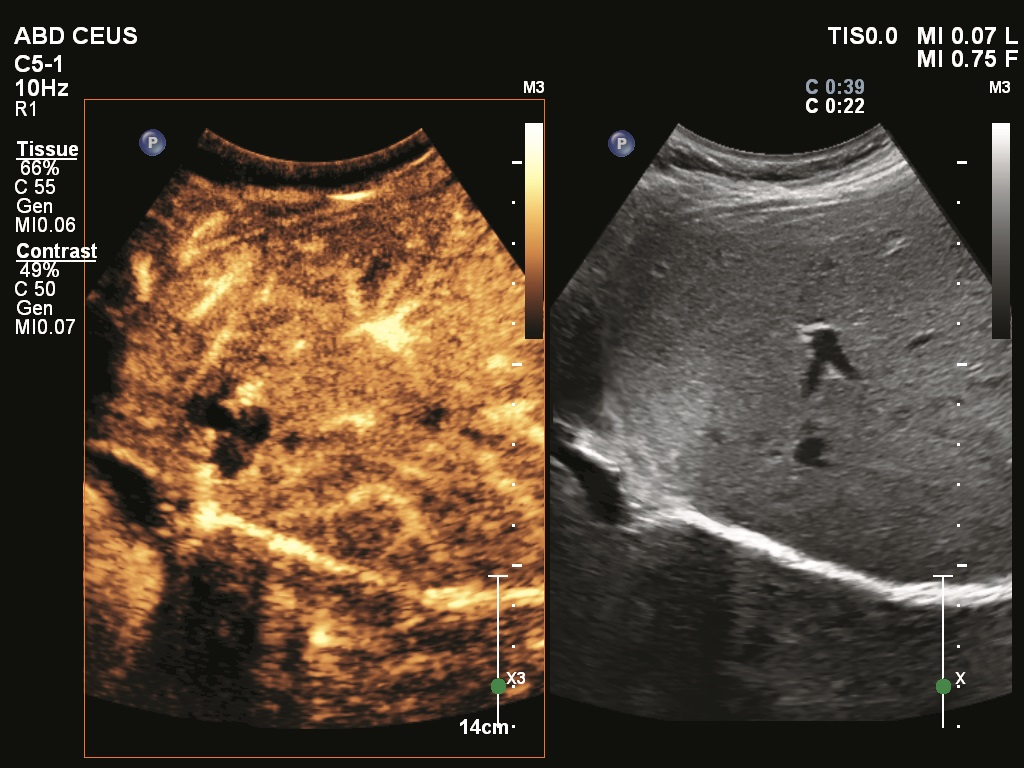

The typical B-mode morphologic and benign elastographic appearances are shown in Figures 1 and 2, and the most common pattern for cancer is shown in Figure 3. In two instances, shear waves do not propagate: in cysts and complicated cysts the lower portion of the lesion may be black, indicating absence of shear waves. More dramatic is the blackness of large irregularly shaped carcinomas, which reject the shear waves but show no ambiguity in their malignant B-mode features and the large multicolor elastographic pattern that surrounds the mass (Figure 3).